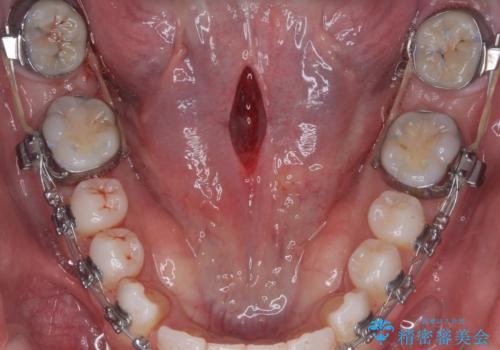

舌小帯の切除

手術自体は当日での処置が可能です。

抜糸は1週間から2週間の期間を置いた後治癒を確認してから行います。